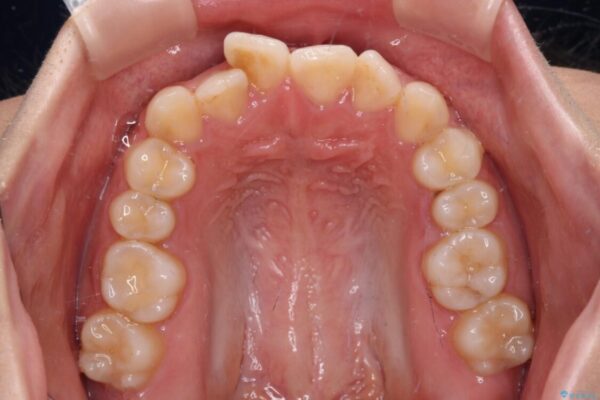

治療途中

• 【モニター】短期間で終わりたい ワイヤー装置での非抜歯矯正 治療途中画像

マウスピース矯正のような自己管理の煩わしさは避け、早く治療を終えたいとのことで、ワイヤー装置による矯正治療を行うこととしました。